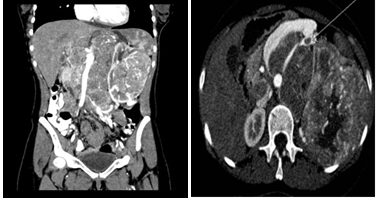

A 20 year old female was referred from a primary care physician with one year history of increasing palpable abdominal mass associated with progressively worsening left flank pain. She reported no other symptoms during this period, except significant anorexia. There was no family history of malignancy ant there were no features suggestive of tuberous sclerosis. On Examination She had a palpable non tender mass arising from umbilical region extending to Pelvis up to the left flank. The mass was firm, immobile and non-tender. A complete blood count revealed a normocytic normochromic mild anemia. The liver function tests were normal and She had normal electrolytes, urea and serum Creatininie levels as well. A CT-Scan abdomen revealed multiple avidly enhancing masses in the retro peritoneum and left kidney. The mass measured 15cm in greatest dimension and appeared to be primarily arising from the retro peritoneum and left kidney (Figure 1a). There were associated necrotic para-aortic nodes. A tumor thrombus was present in the left renal artery (Figure 1b). Rest of the abdominal and pelvic organs was normal.

Figure 1 a) Abdominal CT image, Coronal reformat showing left renal mass and retroperitoneal masses. b) Axial CT image showing left renal artery thrombus.